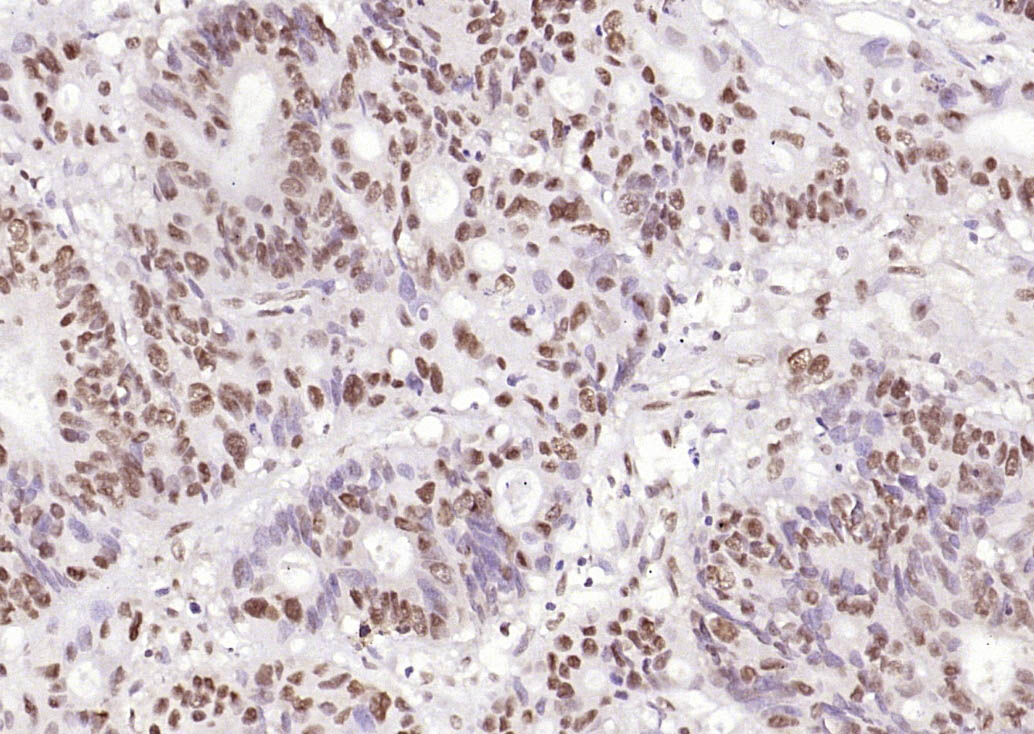

Paraformaldehyde-fixed, paraffin embedded (human rectal carcinoma); Antigen retrieval by boiling in sodium citrate buffer (pH6.0) for 30min; Block endogenous peroxidase by 3% hydrogen peroxide for 20 minutes; Blocking buffer (normal goat serum) at 37°C for 30min; Antibody incubation with (HP1 gamma) Monoclonal Antibody, Unconjugated (bsm-33375M) at 1:200 overnight at 4°C, followed by operating according to SP Kit(Mouse) (sp-0024) instructionsand DAB staining.